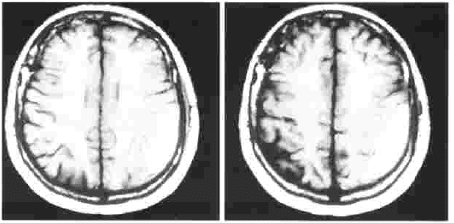

El paciente progresivamente manifiesta síntomas persistentes de cefalea holocraneana, se realiza un nuevo control radiológico al mes del cuadro agudo subdural, y se observa en las imágenes, la formación de un hematoma subdural crónico izquierdo (imagen No. 2). Los familiares refieren que el paciente duerme preferencialmente sobre el lado derecho.

Por las condiciones clínicas del paciente, es tratado solamente controlando la posición de la cabeza durante el sueño, solicitando que duerma del lado don de presenta el hematoma, del lado izquierdo.

Los controles radiológicos muestran la absorción progresiva del hematoma (imagen No. 3), hasta el último control 3 meses después con la absorción completa, se visualiza también en las imágenes la encefalomalacia producida por la lesión vascular en el territorio frontoparietal izquierdo (imagen No. 4).

Imagen No. 2. Resonancia Magnética cerebral 4 semanas después. Se observa un hematoma subdural crónico izquierdo.

Imagen No. 3. TAC de cráneo simple 2 meses después. Se observa la absorción progresiva del hematoma subdural crónico izquierdo.

Imagen No. 4. TAC de graneo simple sin hematoma subdural. Se modificaron las imágenes para eliminar el nombre y los datos del paciente.